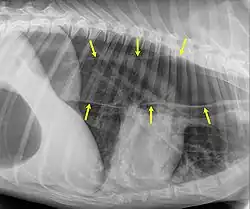

Megaesófago, también conocido como dilatación esofágica, es un trastorno del esófago en humanos y otros mamíferos, donde el esófago se agranda de forma anormal. El megaesófago puede ser causado por cualquier enfermedad que haga que los músculos del esófago no puedan impulsar adecuadamente los alimentos y el líquido de la boca al estómago (es decir, una falla de la peristalsis). Los alimentos se pueden alojar en el esófago flácido, donde pueden descomponerse, regurgitarse o inhalarse en los pulmones (lo que conduce a una neumonía por aspiración).

Megaesófago también puede ser un síntoma de la enfermedad miastenia gravis . La miastenia gravis es una enfermedad neuromuscular donde el principal síntoma es la debilidad en varias partes del cuerpo del perro. Sin embargo, cuando se produce miastenia gravis en perros de edad avanzada, se la considera como una enfermedad inmunomediada . A menudo, cuando se diagnostica miastenia gravis en perros mayores, el primer síntoma que puede manifestar el perro es el megaesófago.

Una distinción importante en el reconocimiento de megaesófago es la diferencia entre cuando un perro regurgita o vomita. Cuando un perro regurgita, generalmente no implica tanto esfuerzo como cuando un perro vomita. A menudo, cuando regurgita, el perro inclina la cabeza hacia abajo y el líquido y / o la comida casi parecen "saltar" de su garganta.

Uno de los principales peligros para un perro con megaesófago es la neumonía por aspiración. Debido a que la comida permanece alojada en la garganta, a menudo se puede inhalar hacia los pulmones y causar neumonía por aspiración. Una forma de evitar esto es asegurarse de que cada vez que el perro coma o beba algo, el perro se siente por lo menos 10 minutos después o se lo coloque en una posición sentada o "rogando". Este trastorno tiene un pronóstico reservado, sin embargo, una técnica de manejo exitosa es la alimentación vertical en una silla Bailey.